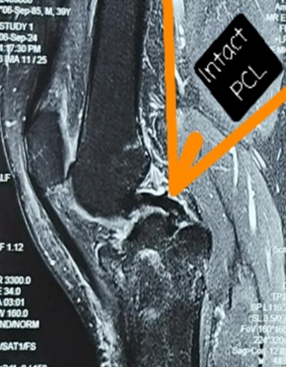

Posterior Approach for Single-stage Fixation of Medial Hoffa with Posterior Cruciate Ligament Avulsion: A Rare Case Report

Meghal Goyal , Kishor Munde

………………………………p.99-103